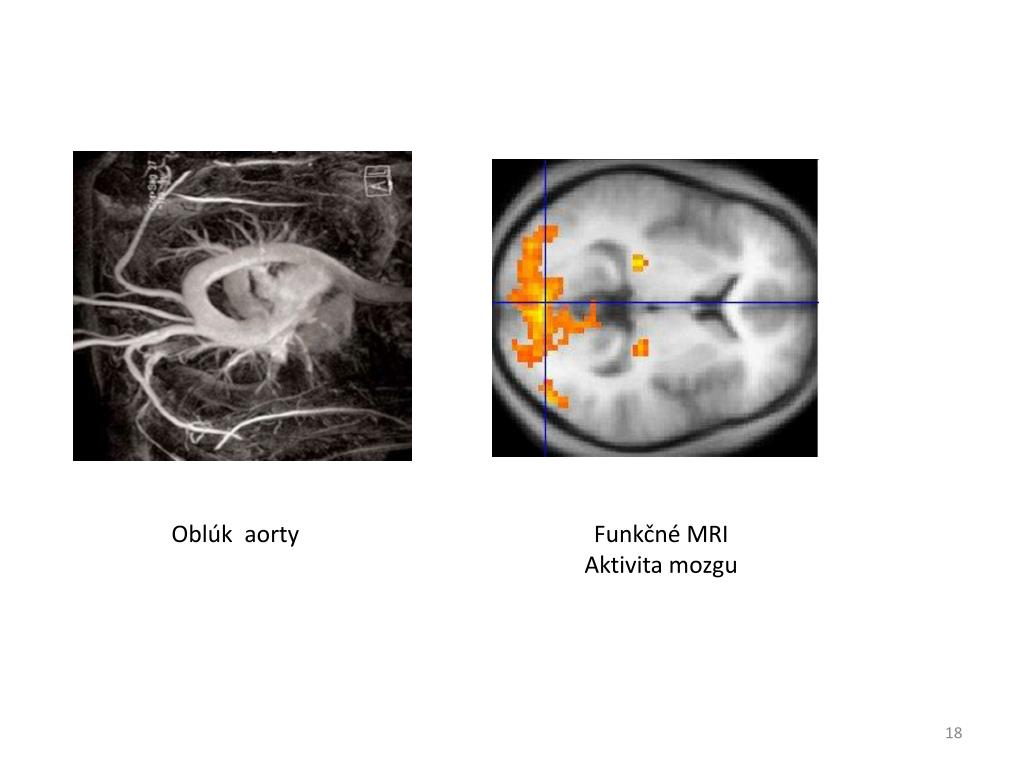

17. Oblúk aorty Funkčné MRI Aktivita mozgu